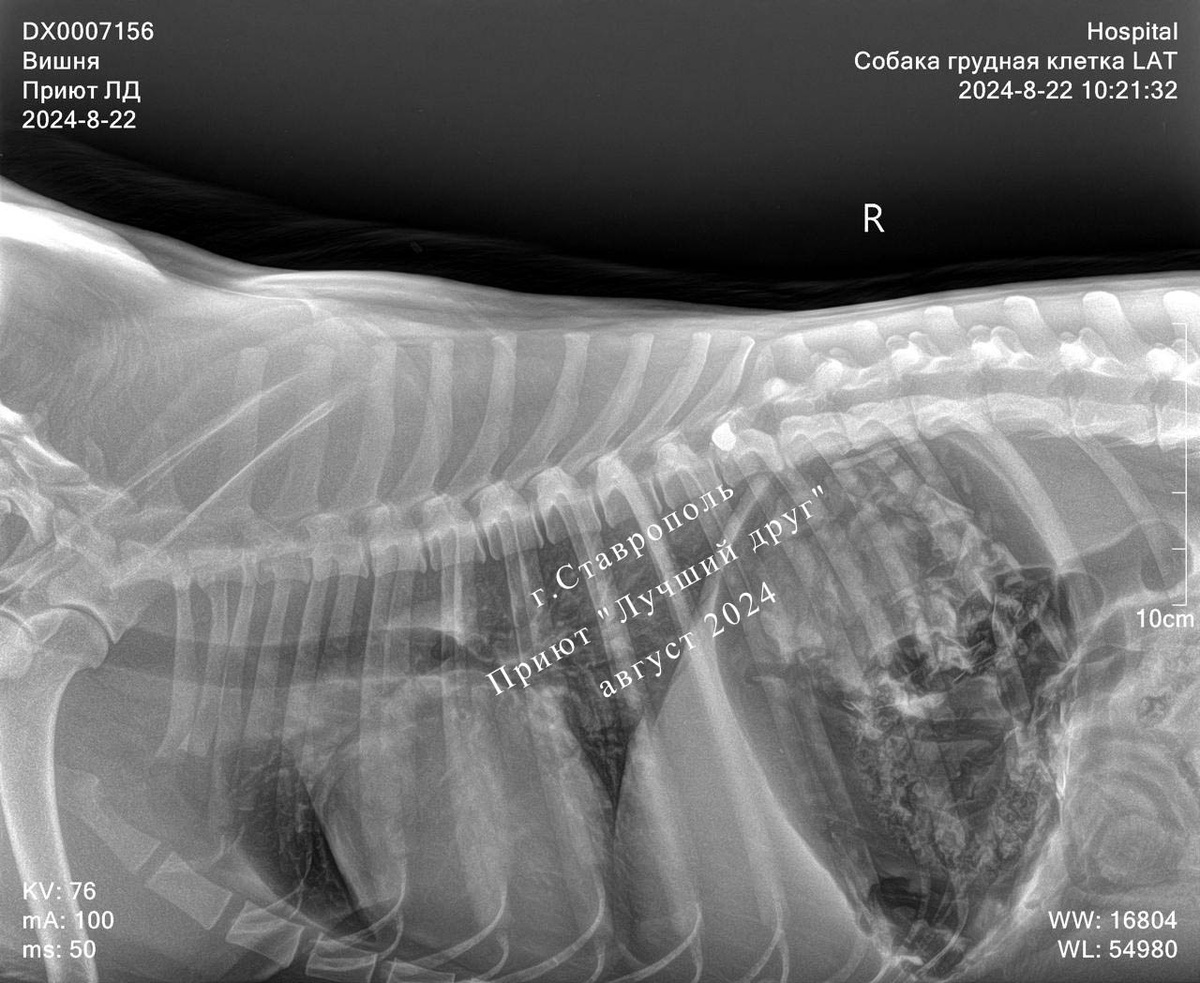

Думали, что собаку сбила машина и у нее сломаны лапы, но всё оказалось значительно хуже, в нее стреляли... У собаки слепое проникающее пулевое ранение грудного отдела позвоночника с компрессией спинного мозга и неврологическим дефицитом. Пулю удалось извлечь, собака перенесла операцию хорошо.